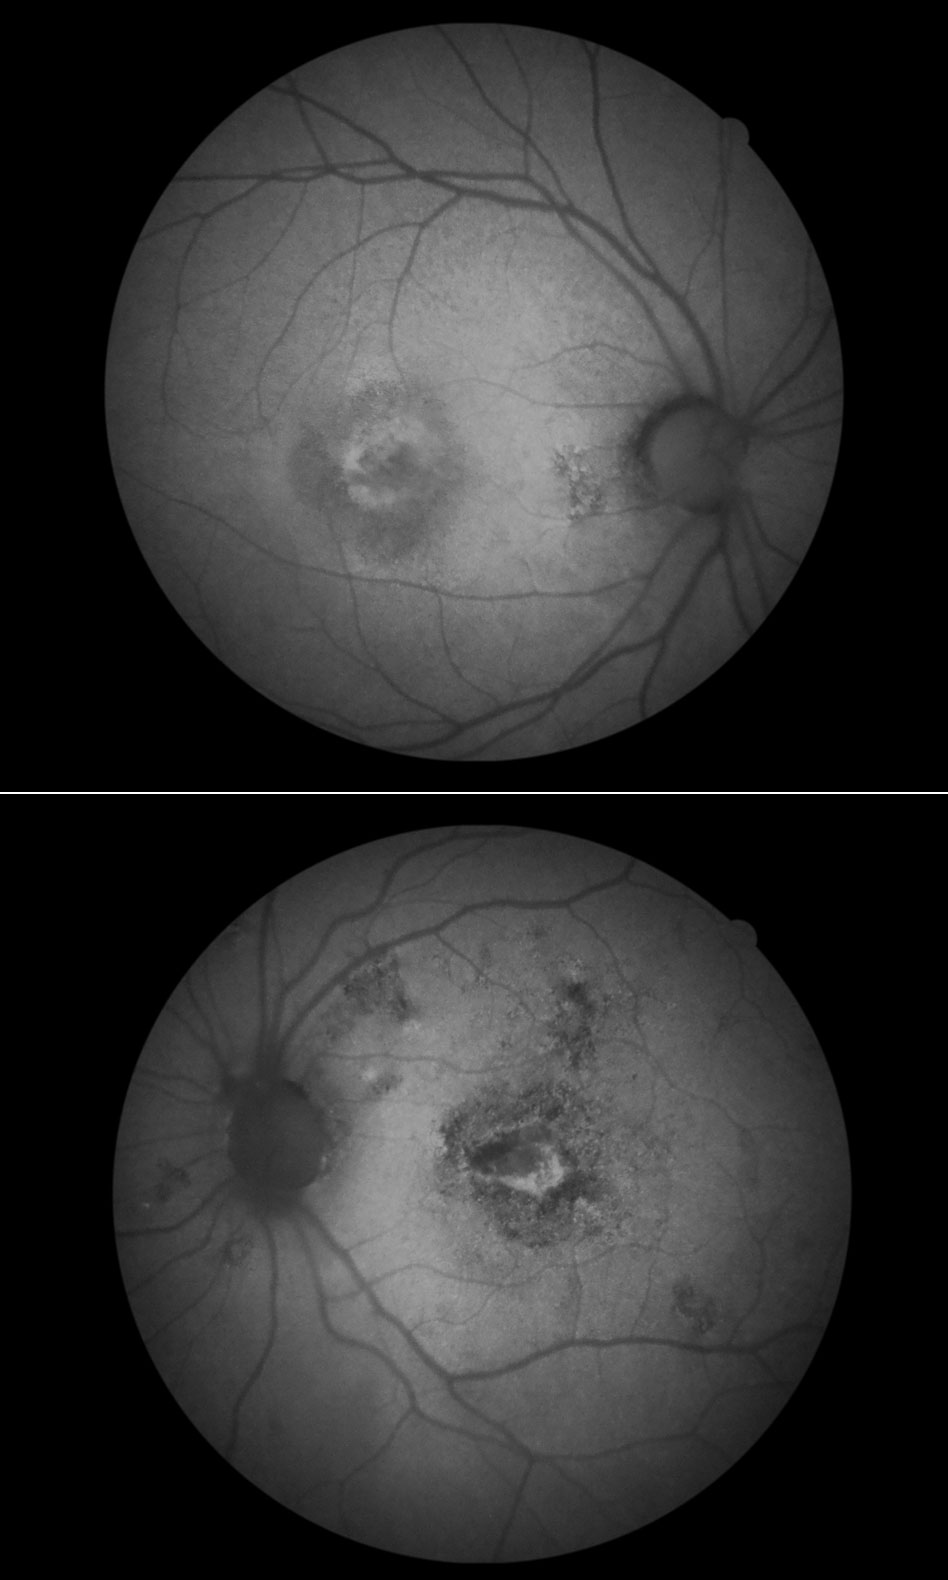

自発蛍光撮影(FAF) :造影剤静注なしで、蛍光撮影できます:加齢黄斑変性等、網膜疾患に使われます。